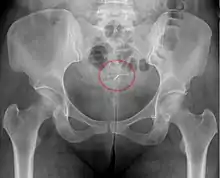

- Una "espiral perdida" ocurre cuando el hilo no puede ser sentido por una mujer en la revisión de rutina y no se ve en el examen con espéculo. Se pueden usar varios dispositivos colectores de hilo o pinzas simples para tratar de agarrar el dispositivo a través del cuello uterino. En los casos poco frecuentes en que esto no sea posible, se puede realizar una ecografía para verificar la posición de la espiral y excluir su perforación a través de la cavidad abdominal o su expulsión previa no reconocida.